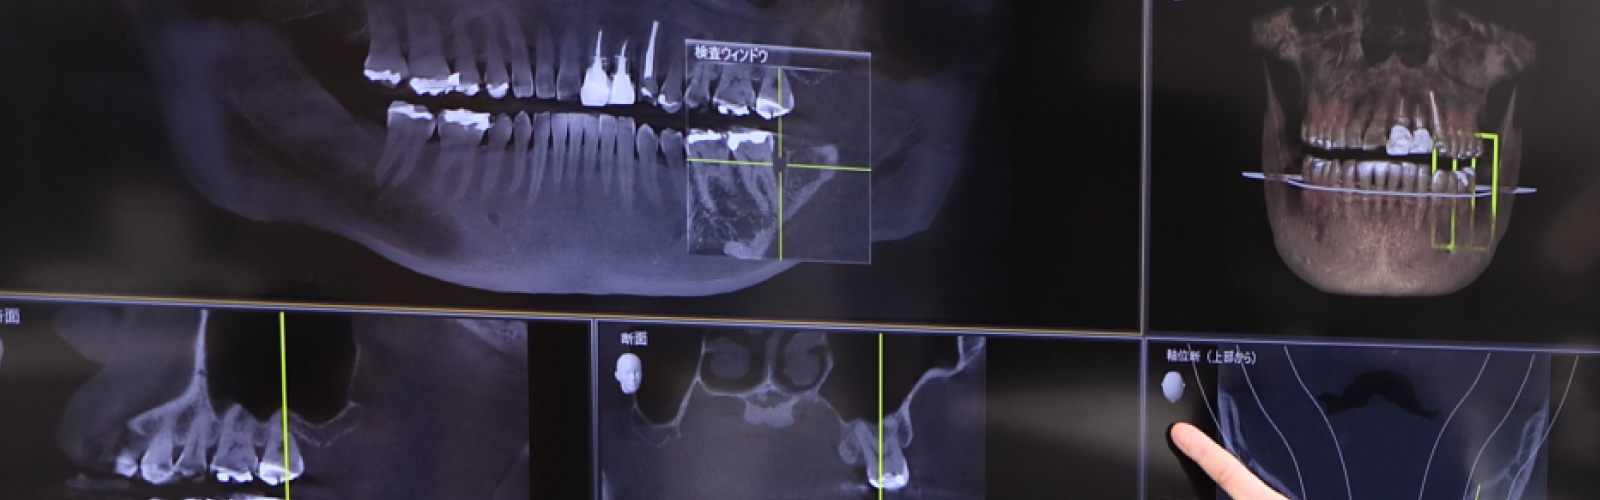

診査・診断・治療計画

診査・診断・治療計画は、オールオン4を成功に導くために必要なとても大事なステップです。

3Dスマイルデザイン、ワックスアップ、ラジオグラフィックガイド等によるプランニングに基づいて、患者様それぞれに合わせたオーダーメイドの治療を慎重に進めていきます。